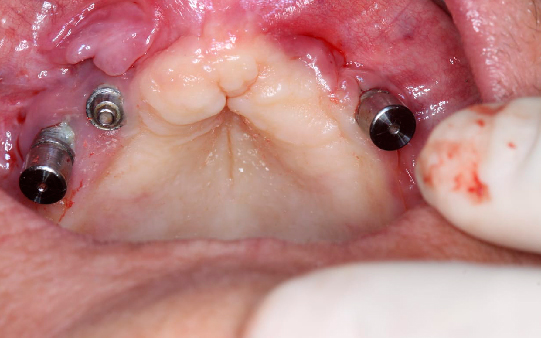

Protocolo em Resina Acrílica: boa estética, acessível, indicado para reabilitações com ótimo custo-benefício.